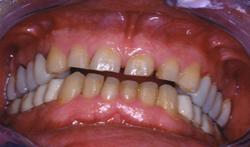

Vue intra-buccale en occlusion

Couronnes tout céramique. Présentation d’un cas clinique : Patient d'une quarantaine d'année bruxomane, présentant des douleurs cervicales et des céphalées matinales. Il existe aussi une perte de la dimension verticale d'occlusion.

Patient d'une quarantaine d'année bruxomane, présentant des douleurs cervicales et des céphalées matinales.

Il existe aussi une perte de la dimension verticale d'occlusion.